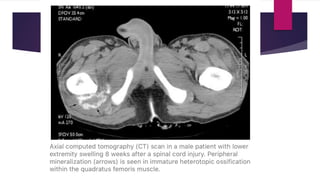

 CT scan – Reveals zonal phenomenon with a rim of calcification of

varying thickness at periphery while central area similar to muscle.